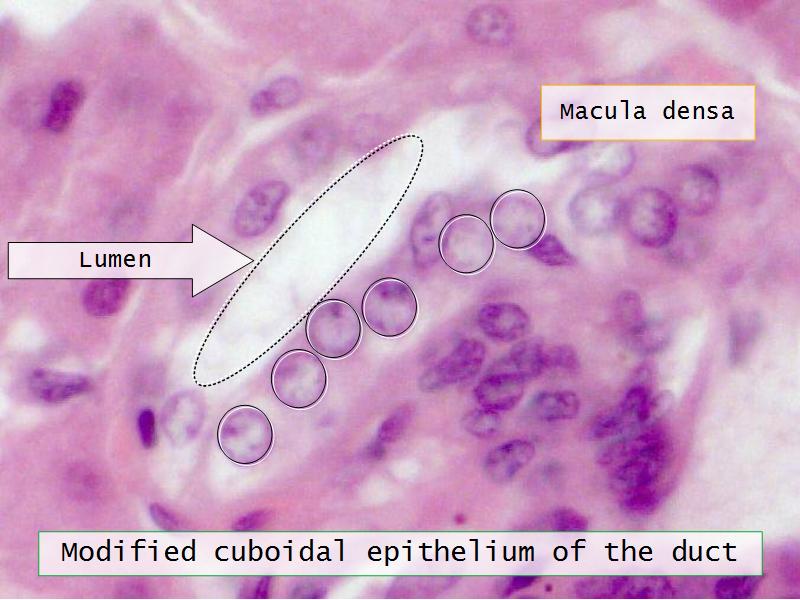

- Basic arrangement of nephrons and collecting tubules in the kidney

- Structure of the nephron and collecting tubules

- The renal corpuscle

- Make an annotated diagram of a nephron, including the juxtaglomerular apparatus. Indicate the flow of blood and water in each part, and how solutes are filtered, secreted and reabsorbed.